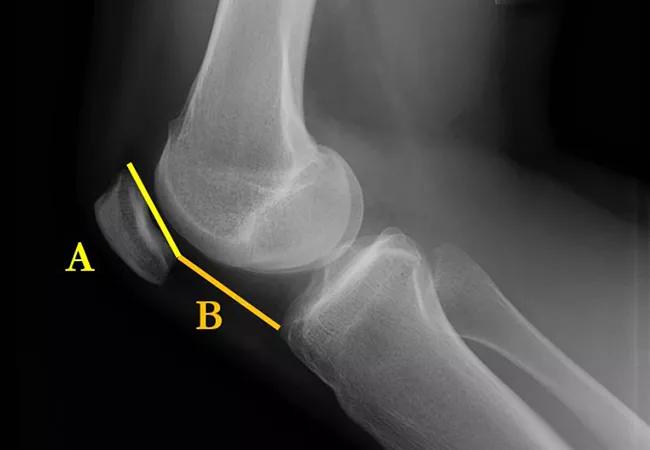

We generally use plain X-ray to evaluate patellar height and trochlear dysplasia. We use the Caton-Deschamps index to evaluate for patella alta (Figure 1). A value above 1.2 is considered abnormal. Trochlear dysplasia is best seen on a perfect lateral X-ray and graded using Dejour classification (Figures 2 and 3).

Figure 1. Caton-Deschamps index. The distance from the inferior articular surface to the anterosuperior corner of the tibia (B) is measured by length of the patellar articular surface (A).